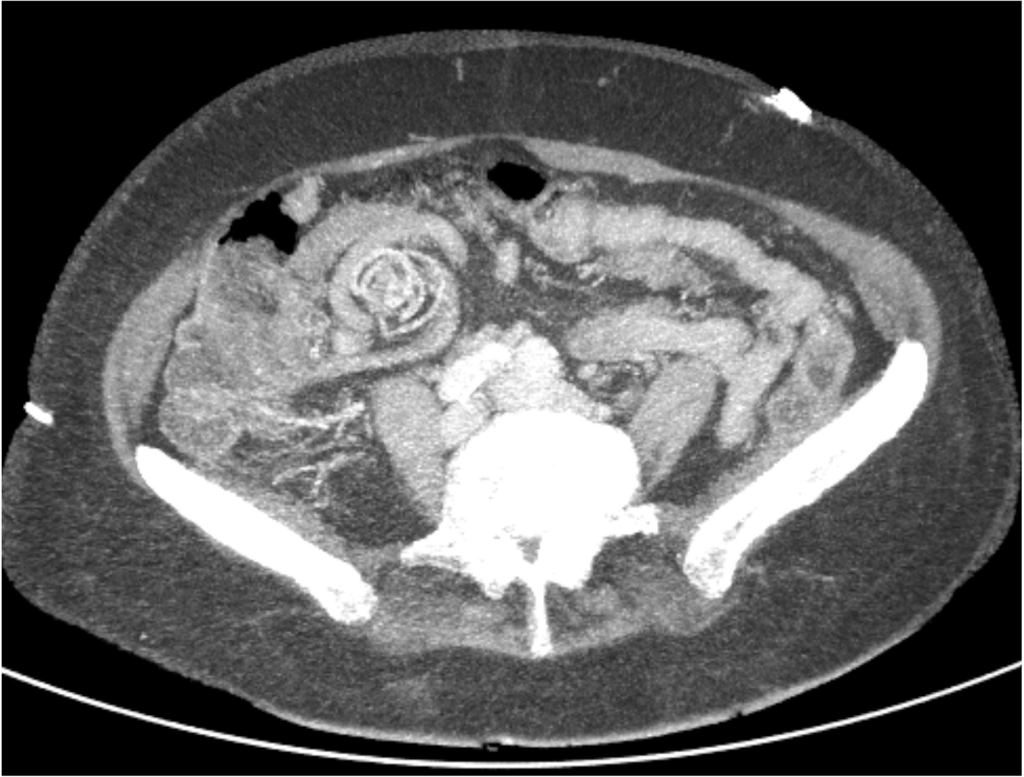

CT-angiogram

Een 80-jarige vrouw komt bij de Spoedeisende Hulp wegens een sinds 12 uur bestaande koliekachtige buikpijn en braken. De buikpijn verdwijnt weer, maar de uitstraling naar de rug verergert. In haar voorgeschiedenis staan een cholecystectomie en een gedilateerde thoracale aorta. Er werd een CT-angiogram van de totale aorta gemaakt.